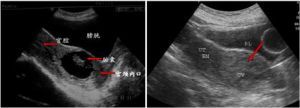

發病機制還不明確,可能與孕卵運行過快、剖宮產引起子宮內膜間質蛻膜缺乏;受精卵著床,發生底蛻膜缺損;滋養細胞直接侵入子宮肌層,並不斷生長,絨毛與子宮肌層粘連、植入甚至穿透子宮壁等有關。普遍認為本病病因是各種手術操作所致的內膜損傷,如刮宮術、剖宮產術、子宮肌瘤剔除術、子宮成形術、宮腔鏡甚至手取胎盤術等。本病的臨床表現並沒有特殊性,患者均有剖宮產史,有停經史、子宮體增大、血HCG升高等正常早孕表現。超聲是診斷本病的可靠方法,子宮瘢痕部位妊娠具有較特異的影像學表現,聲像圖特點為宮內孕囊或胎盤組織位置低,位於子宮下段切口瘢痕處,與切口肌層無分界,孕囊與切口間血流豐富,子宮下段前壁中等回聲,回聲不均,達漿膜見血流,孕囊種植下段前壁切口處,宮頸無異常。